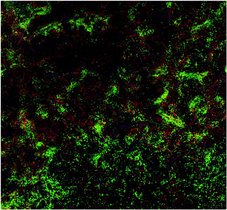

Wie kann man magnetische Bakterien zur Bekämpfung von Krebsgeschwüren nutzen, dies wollen Forschende der ETH Zürich herausfinden. Sie haben nun einen…

Einen neuen Ansatz zur Therapie von Darmkrebs konnten Forschende aus dem Georg-Speyer-Haus in Frankfurt und der Goethe-Universität Frankfurt in einem…